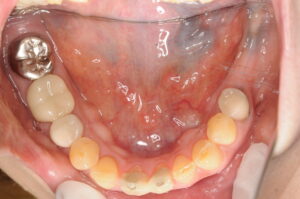

![]()

治療後の経過

治療開始から約1年9ヶ月を経て、左下奥歯2本がインプラントで再建されました。両側でバランス良く噛めるようになり、長年抱えていた咀嚼の不自由さが解消されました。